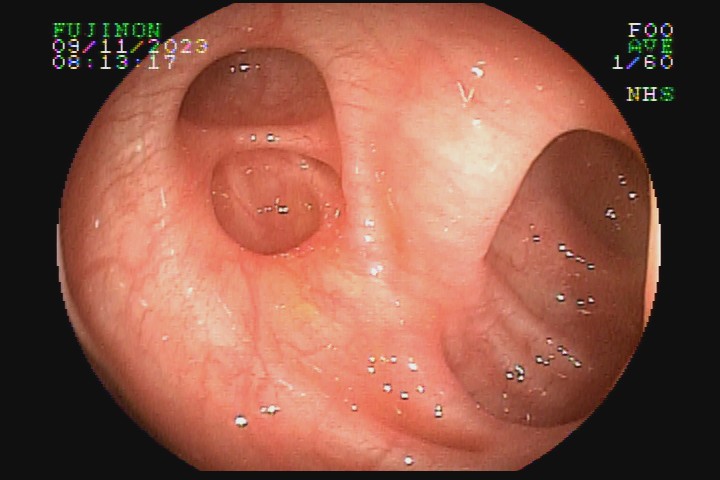

A diverticulose é uma doença adquirida, frequente entre pessoas mais idosas. Acredita-se que tenha como principal fator etiológico hábitos dietéticos relacionados com o refinamento da dieta industrializada. Pode ter uma evolução benigna por toda a vida e ser totalmente assintomática, mas pode também caracterizar-se como doença de sinais e sintomas agressivvos, com considerável morbidade e mortalidade devido às suas principais complicações: inflamação e sangramento.

A diverticulose cólica é consequência da herniação da mucosa do intestino grosso por entre as fibras musculares da parede intestinal. A diverticulose do cólon esquerdo complica mais com inflamação, e a diverticulose do cólon direito complica mais com sangramento.